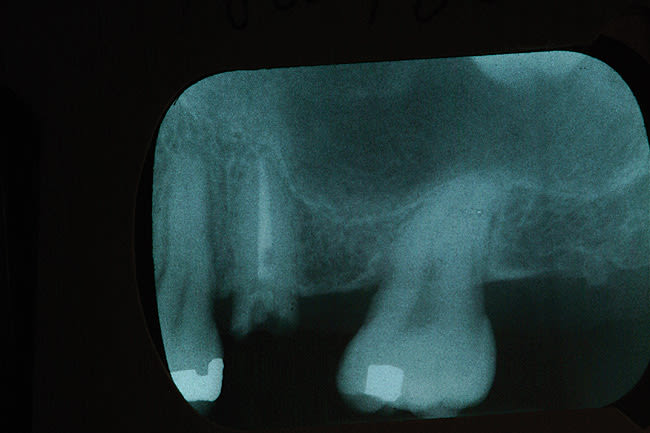

A 39-year-old woman was seen for evaluation, wanting her recently fractured upper left second bicuspid (x-ray pictured in Figure 1) repaired. She reported a prior dental history of an abscess that had developed under a large silver filling and, to resolve the problem, she had undergone endodontic treatment and had a traditional porcelain-fused-to-metal (PFM) crown put in. She was chewing on an almond when the tooth cracked and the crown came off. Clinical examination suggested that the root was too short to lengthen surgically. It was decided to remove the tooth and place a dental implant. The extraction site did not require bone grafting to maintain the width of the ridge.

A 4.3-mm diameter Hiossen implant (www.hiossen.com) was placed and maximum torque of 60 newton centimeters was achieved. The implant used in this case had microthreads on the top quarter of the implant and the abutments placed were narrower than the head of the implant. This relationship of decreased abutment/implant diameter is described as platform switching. The implant was fully integrated and uncovered in 4 months, with a temporary abutment placed (Figure 2). With an internal connection design—which can create an optimal condition for the preservation of crestal bone—providing a more rigid connection from a mechanical standpoint,10 the implant was restored using a traditional PFM crown, which established optimal emergence profile. Figure 3 shows the crown in place for 18 months, with no tissue inflammation.